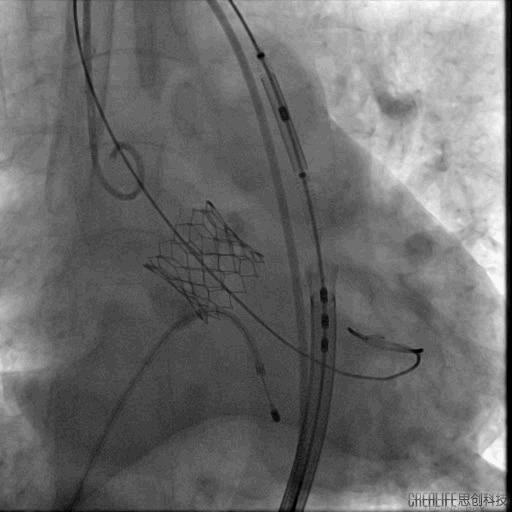

危险在此时发生了,球囊扩张后,患者出现血压下降,造影发现钙化的瓣膜扩开后出现大量反流,手术团队当即决定马上植入已经预装好的23号瓣膜,且因为预扩张球囊的反馈情况,把原有定额17ml减少2ml至15ml,成功跨瓣后精确定位并在临时起搏器180次/分起搏控制血压下于高位释放,过程顺利。

球囊扩张后重度返流

瓣膜定位

瓣膜释放

然而瓣膜释放后患者出现室颤,再次面临命悬一线的险境,术者团队处危不惊,快速予以除颤处理,患者成功恢复为窦性心律,转危为安。

复查造影示轻度主动脉瓣返流,同时行床边经食道心脏彩超,未见明显瓣周漏,瓣膜功能良好。升主动脉压力156/92mmHg,跨瓣压差<10mmHg。患者生命体征平稳,送返病房,密切监测生命体征变化。

最后造影